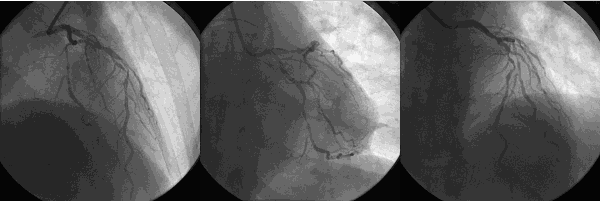

急诊冠脉造影

造影时间:2015年07月19日。

造影前用药:造影前给予替格瑞洛180 mg、肝素3000单位。

造影结果1:右冠近中段原支架未见明显狭窄。

造影结果2:左主干正常,左前降支近段100%闭塞,回旋支中远段80%~90%狭窄。

![]()

造影结论及应对策略:本病例行冠脉造影发现: 右冠近中段原支架未见明显狭窄,左主干正常,左前降支近段100%闭塞,回旋支中远段80%~90%狭窄。立即行前降支PCI术。